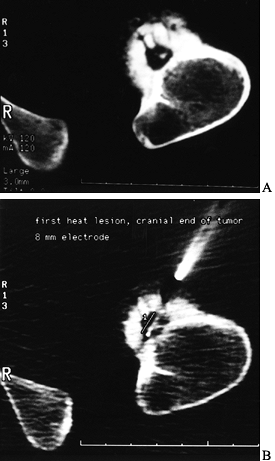

institutions for lesions outside the spine (8,119,131). The technique involves introducing a radiofrequency probe over a biopsy needle, placed under CT control (Fig. 127.2).

![]() |

|

Figure 127.2. A:

The CT of another patient with an osteoid osteoma on the cortex of the proximal femur. The nidus is mostly radiolucent with a central radiodensity, and there is thick periosteal new bone around it. B: The trochar being placed into the lesion for radiofrequency heat ablation under CT control. The patient is under general anesthesia. |